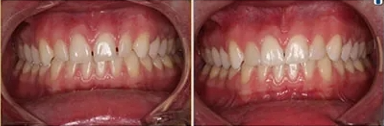

Interceptive orthodontics is an early intervention for growing children. Children from first to third grade are prime candidates for early orthodontic intervention, as the face rapidly grows during this time. With this method, specialists coordinate care with other medical specialists to help direct facial growth and improve the overall health and function of the mouth.

Orthodontic arch development can often make room for permanent teeth, thus eliminating extensive treatment times. Dental crowding is addressed early when the face has significant growth potential. The correct mode of breathing (through the nose) is related to dental crowding, and more mouth breathing will result in more dental crowding.

Interceptive orthodontic treatment provides multiple benefits, including reducing the need for extensive treatment later, improving breathing, improving facial growth, improving dental arch development, and avoiding the loss of permanent teeth while giving your child a fantastic confidence-boosting smile.

Early interceptive orthodontic treatment is intended for the growing child at a much younger age than for traditional braces. The old adage of waiting until all the baby teeth fall out is no longer valid. Better results can often be attained by addressing early crowding and monitoring facial growth โ waiting for all the baby teeth to be lost may not be the best option for your child.

That's why we offer early orthodontic interceptive treatment right here at our pediatric dentist's office in Boerne, TX, particularly during the first few years of life (birth to age 4).

Children with moderate to severe dental crowding will benefit from interceptive or early orthodontic treatment. Parents typically notice crowding when the lower front permanent teeth first appear around age 6 years. At The Kids Place, our pediatric dental team will evaluate patients' smiles early on, when permanent teeth should be coming in, if they are crowded, when they are delayed, and when they are coming in out of position.

By recognizing and addressing orthodontic concerns early, we can often eliminate future extractions of permanent teeth, improve overall health and function of the mouth, and help give your child a beautiful smile.